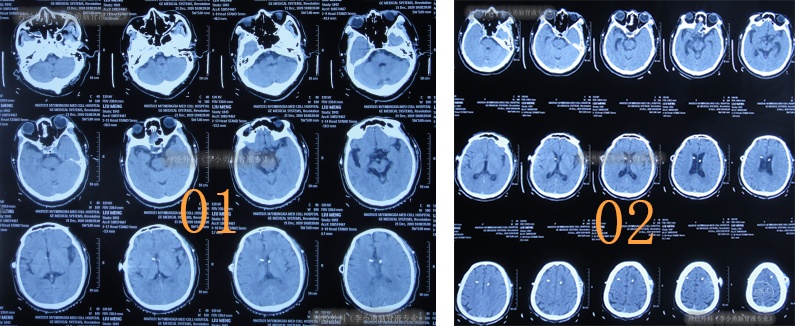

术后次日查头颅CT示脑室有缩小(图-4),意识也有好转。

图-4:2020年12月9日头颅CT